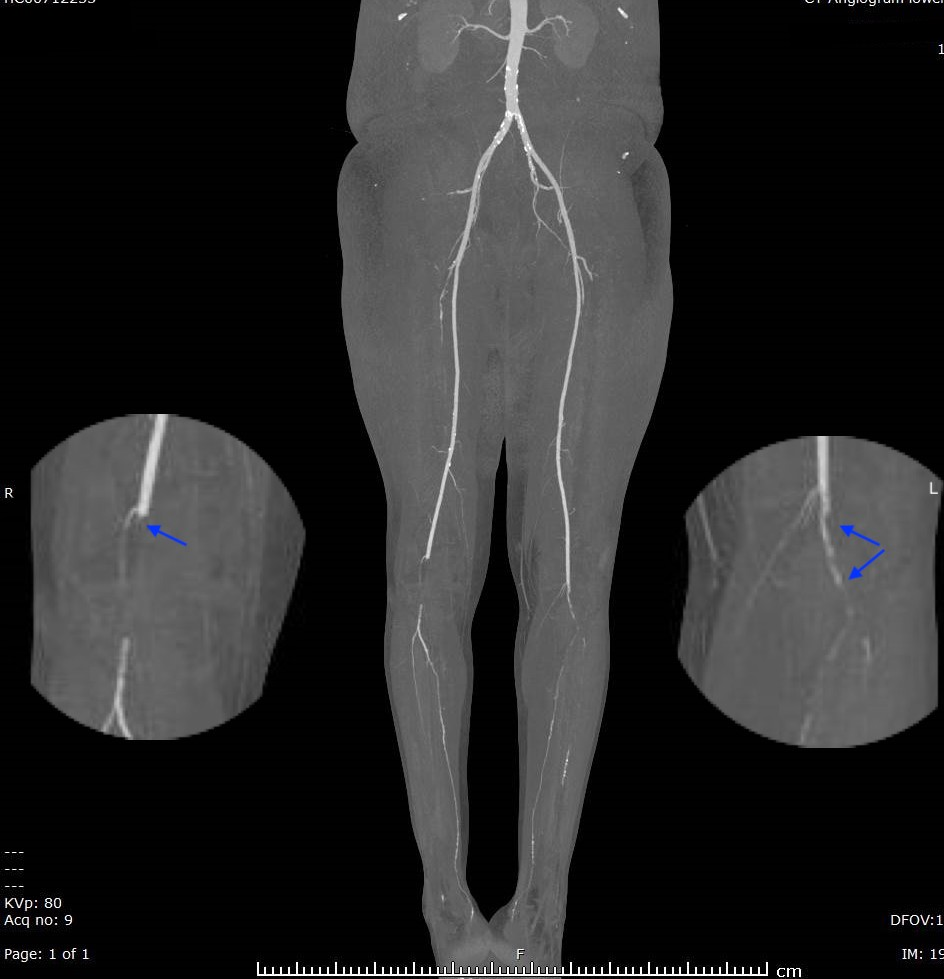

From www.ctisus.com

Occlusion of the Common Illiac Arteries Bilaterally Vascular Case What Is Occlusion Of Artery When this supply is cut. It can cause shortness of breath and chest pain but. The location of the clog, or occlusion, dictates the signs and symptoms. Vascular occlusion is a blood vessel blockage that prevents blood from moving through pathways in your body. Arteries carry blood that is full of oxygen and nutrients to every cell in your body.. What Is Occlusion Of Artery.